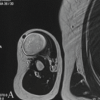

A 75-year-old male with a history of type 2 diabetes and treatment completed tuberculosis presented in outpatient department for evaluation of right olecranon bursitis. The patient has had a painless swelling over his right elbow for 3 years with no associated history of trauma. Swelling started to drain purulent pus for the past 1 month which was when the patient had sought medical attention. The patient was then treated with multiple antibiotics but with no relief. On examination, the patient had an enlarged, thickened, and fluctuant right olecranon bursa of 5 cm diameter with copious purulent pus drainage. There was no overlying cellulitis or lymphadenopathy. Range of movements of right elbow was full and painless. Radiographic evaluation showed a soft-tissue swelling over the olecranon without any osseous involvement or joint space reduction. Blood leukocyte count was within limits. A bacterial culture was sent which came back negative. Surgical excision of the bursa was performed under brachial plexus block. Intraoperative examination revealed a thick-walled bursa filled with purulent material. The bursa was excised and sent for histopathological examination (Fig. 1 and 2).